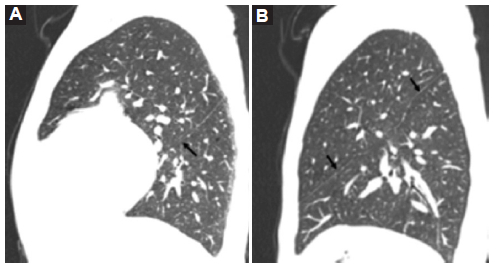

Pulmones y bronquios

El síndrome de heterotaxia con isomerismo izquierdo se asocia a pulmones simétricos, bilobulados con una única cisura, como se observó en los casos 1, 2 y 3 (Figs. 3 y 4).

Los bronquios fuente son largos bilateralmente y pasan por debajo de la arteria pulmonar correspondiente, comportándose ambos como bronquios fuente izquierdos. Presentan bifurcación anatómica izquierda (bronquio lobar superior e inferior) y la distancia entre la carina y la primera división del bronquio princial es igual en ambos pulmones.